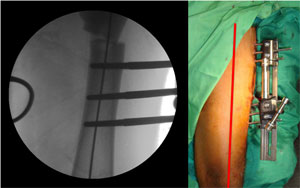

The pictures taken during surgery, showing the position of the Schanz screws and their orientation in different planes. |

The C-arm picture on the left and the clinical picture showing the perfectly aligned axis. |